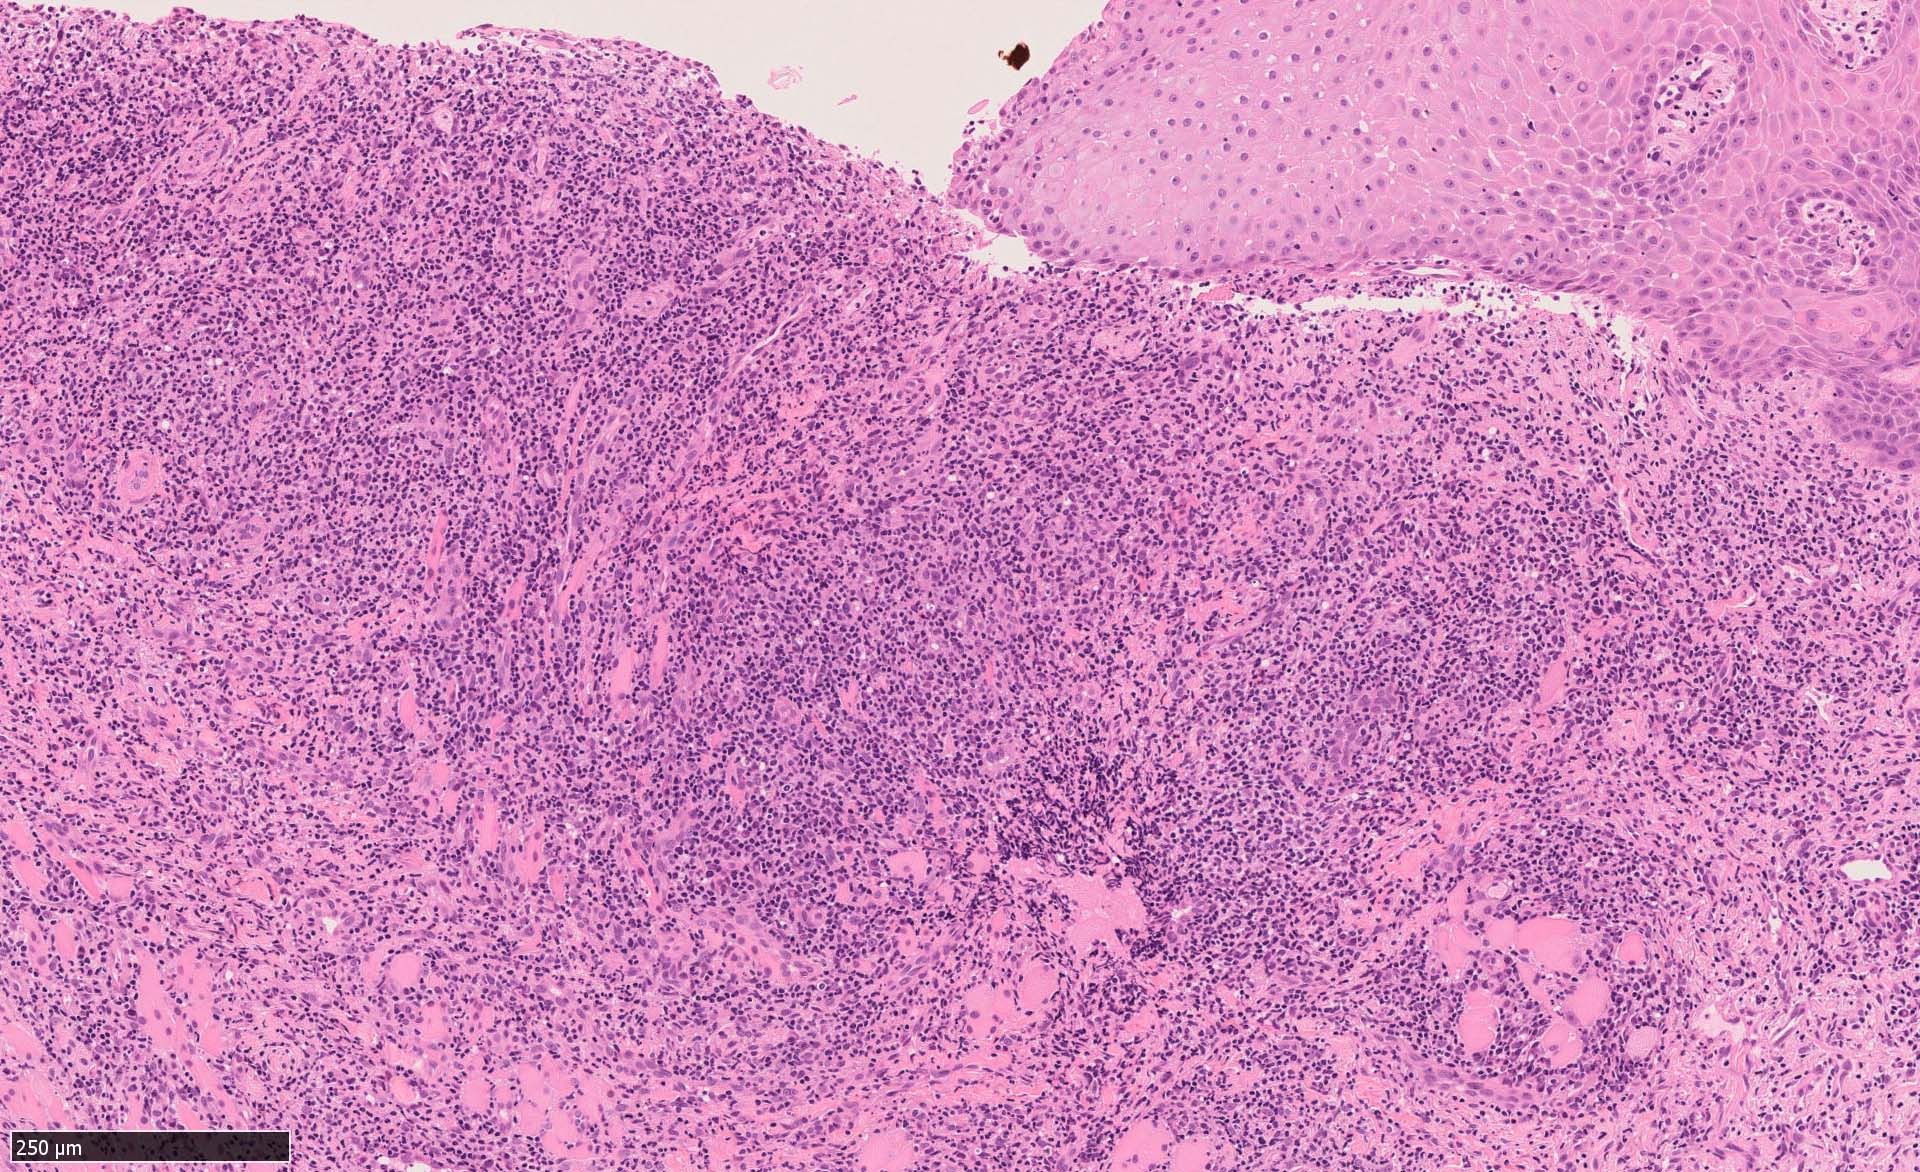

EBV陽性粘膜皮膚潰瘍(EBVMCU)は、EBV陽性の異型大型B細胞および/またはHodgkin/ Reed-Sternberg (HRS)様細胞を含む多形リンパ球浸潤を伴うリンパ増殖性疾患(pleomorphic pattern)で、

典型的には免疫不全/調節障害を有する患者の粘膜および皮膚に発現する。--WHO 5th classificationに記述された定義

定義上はB細胞系のLPDをEBVMCUとしている.

IWT case